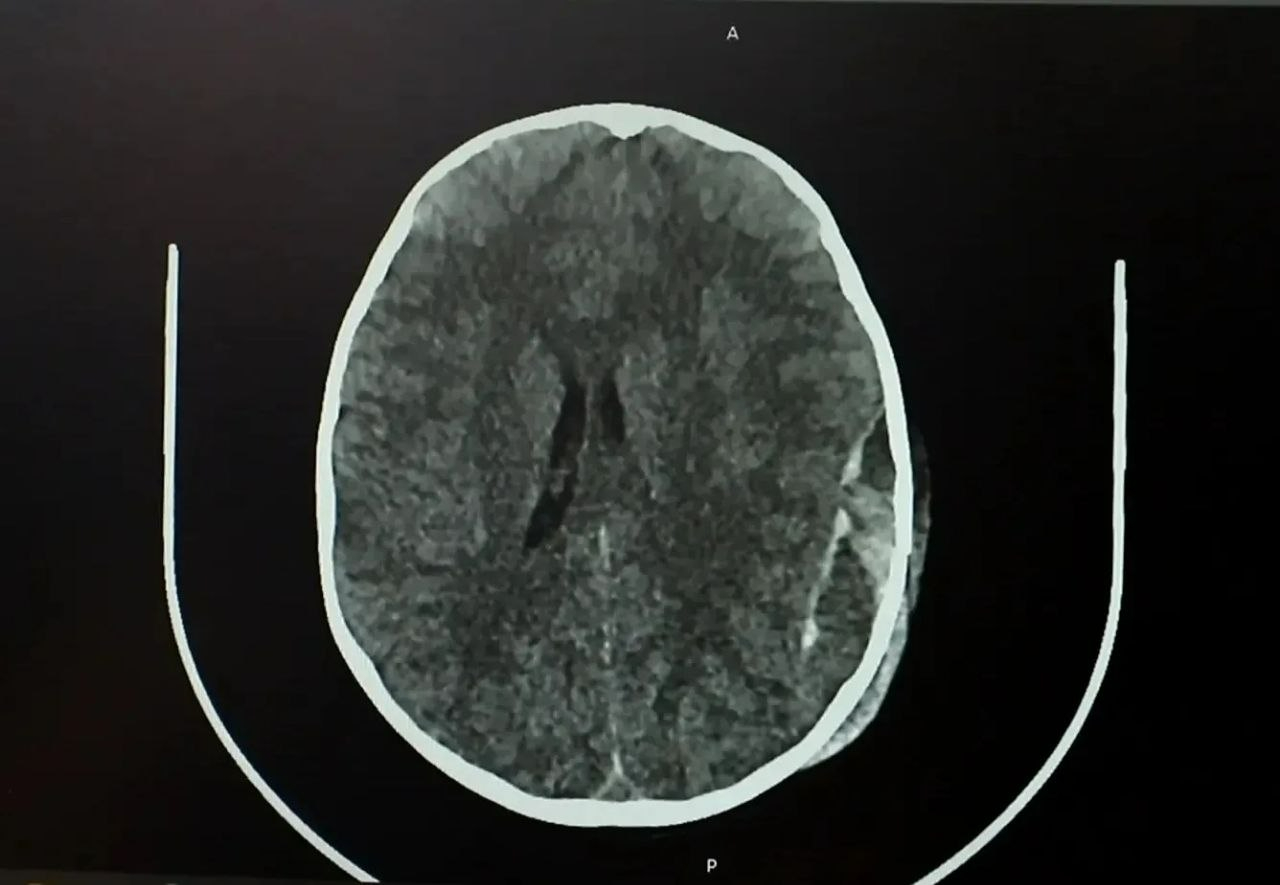

Как сообщает Минздрав Кузбасса, сразу после происшествия у ребёнка не было видимых травм головы, однако на следующий день он начал отказываться от еды. Родители обратились в больницу, где обследование выявило серьёзные повреждения – перелом черепа и острую эпидуральную гематому.

Мальчика экстренно доставили в операционную. Нейрохирурги провели сложную операцию – костно-пластическую трепанацию черепа, удалили гематому и остановили кровотечение.